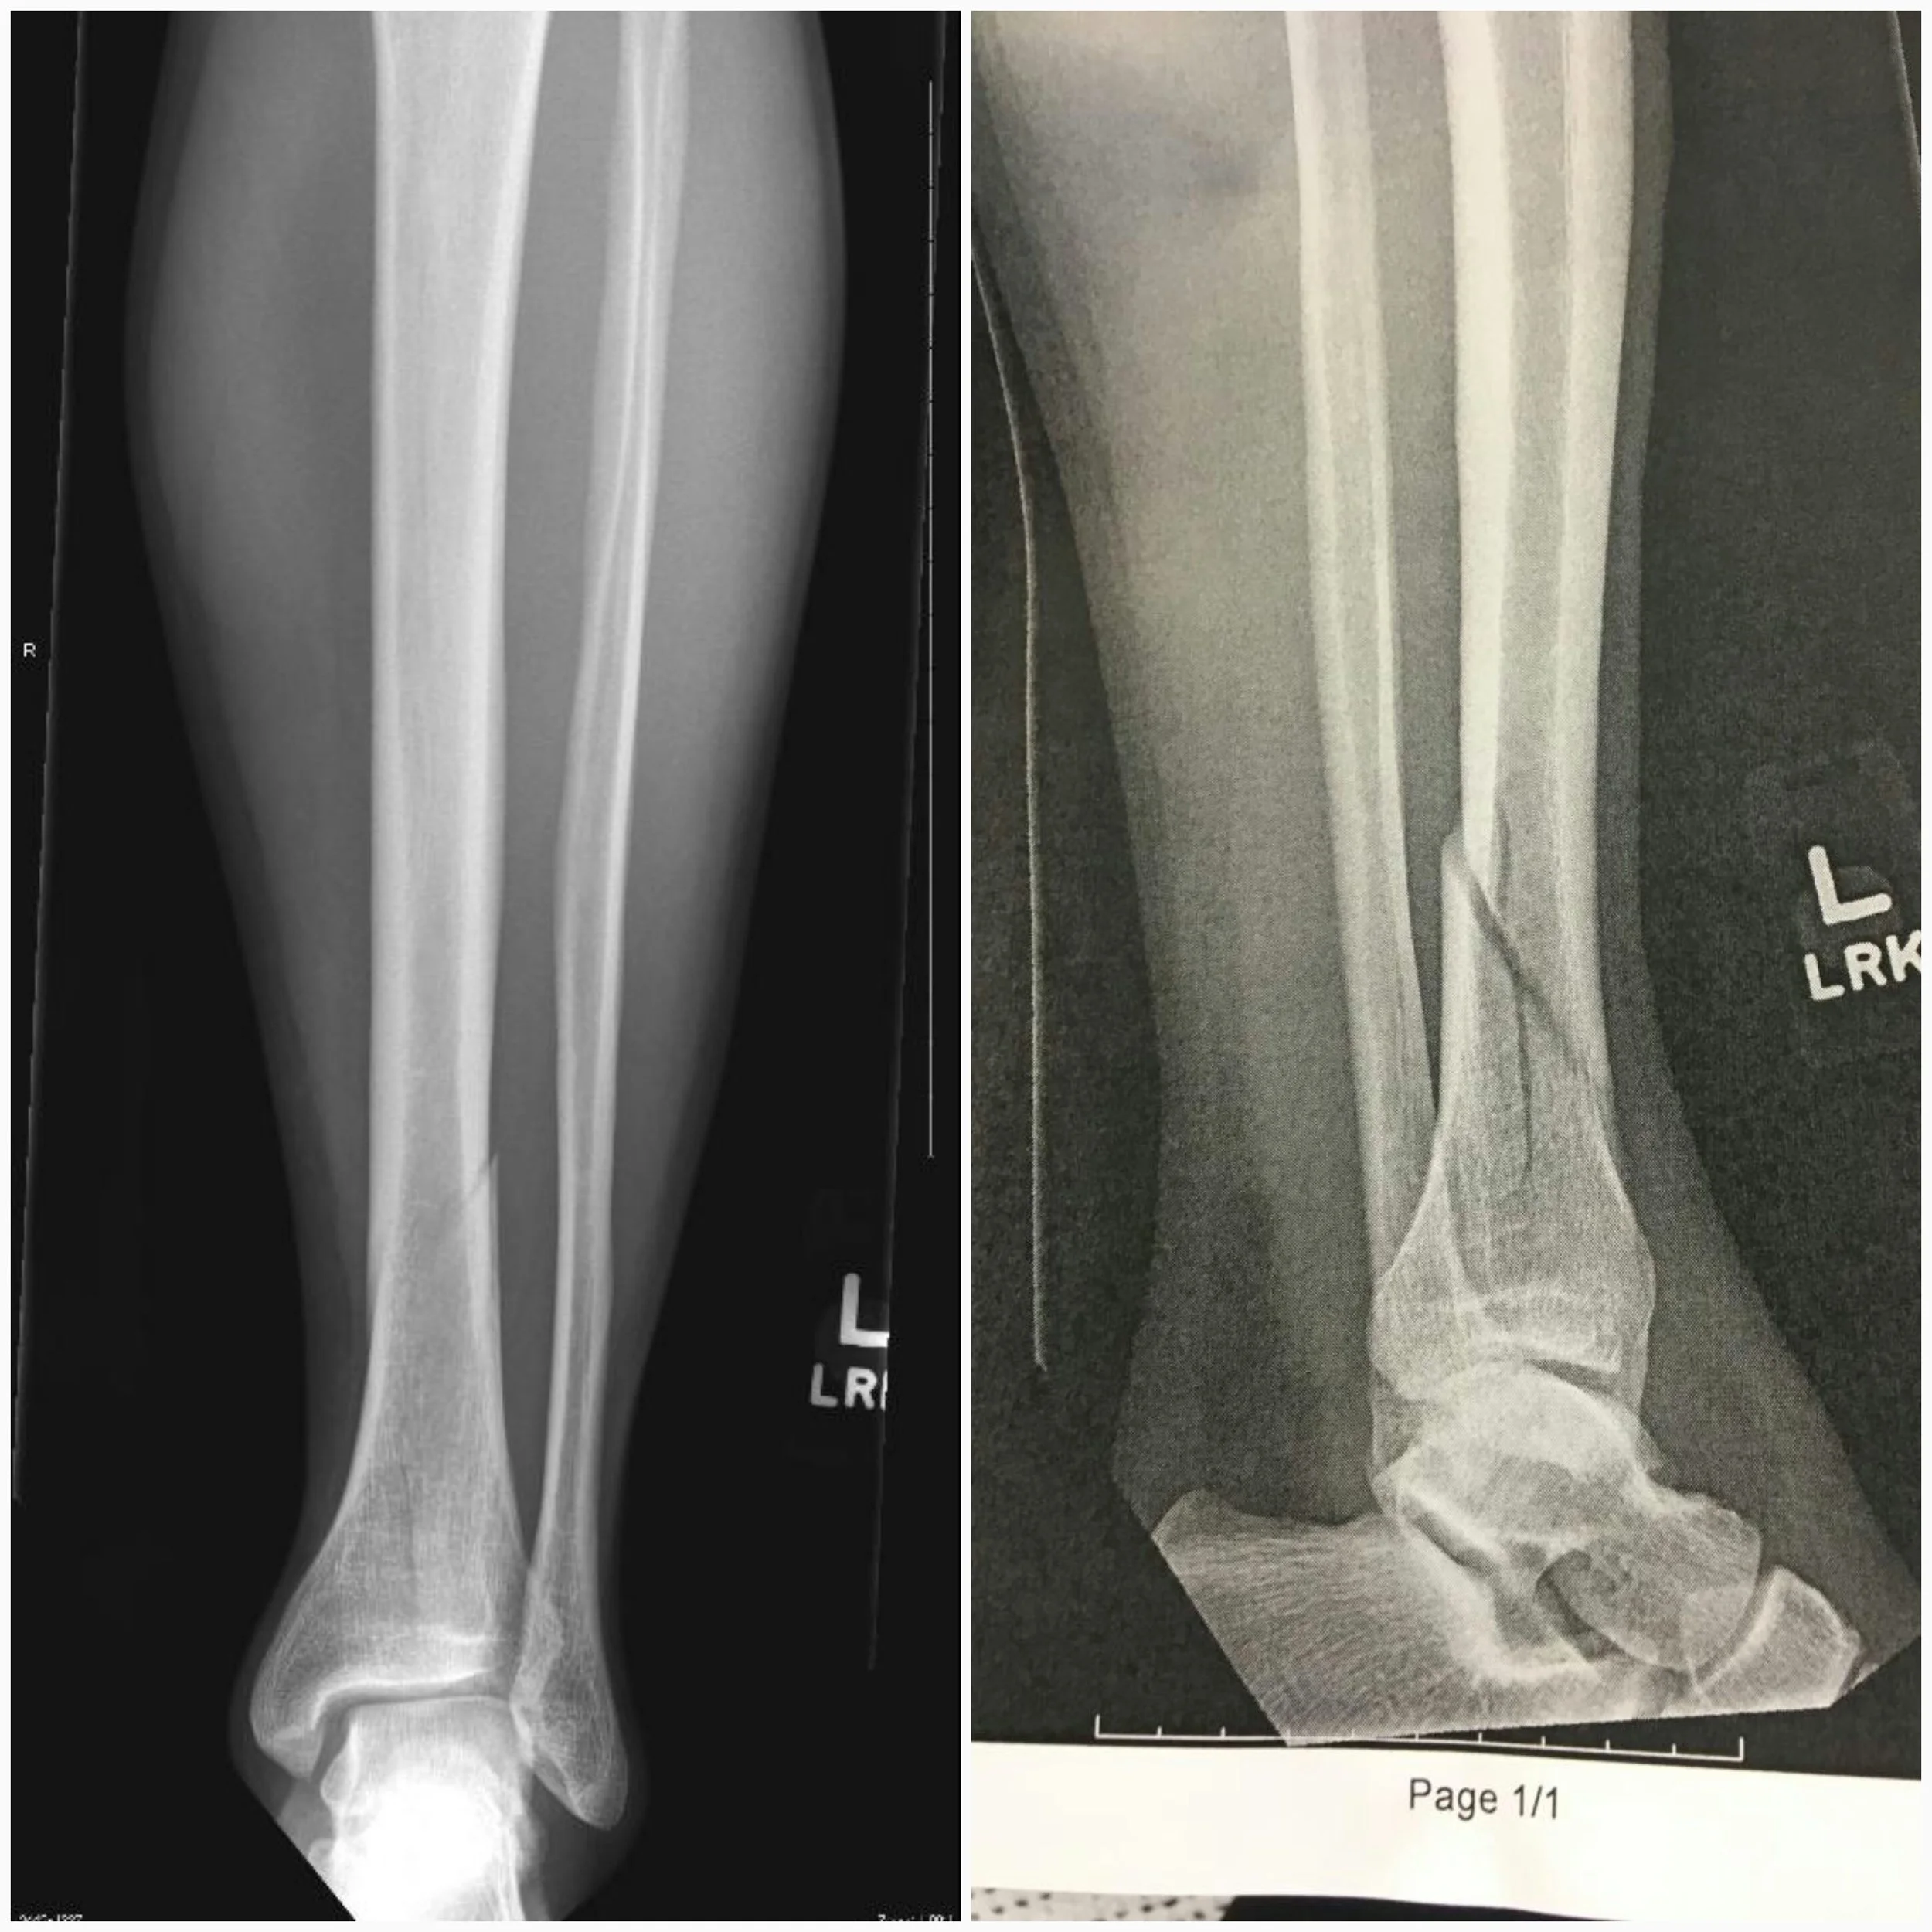

I can't recall the exact time and wording, but I received a text from Ben later that day saying that the X-ray results showed a fractured tibia and that they put him in a boot. It was accompanied with the picture below...

Now...I was expecting the results to yield a fracture of some type, but not to the extent that had actually occurred. It appeared to me that Ben had sustained an unstable spiral oblique fracture. The first picture view is from the front and you can see the break but the real damage is shown in the 2nd, lateral view. In this, the slippage of the tibia as well as the break on the bias (oblique) is visible as well as a noticeable vertical break along the length of the bone.